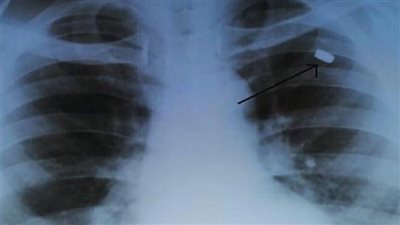

أصيب بها قبل 30 عاما.. أطباء يستخرجون رصاصة من صدر رجل!